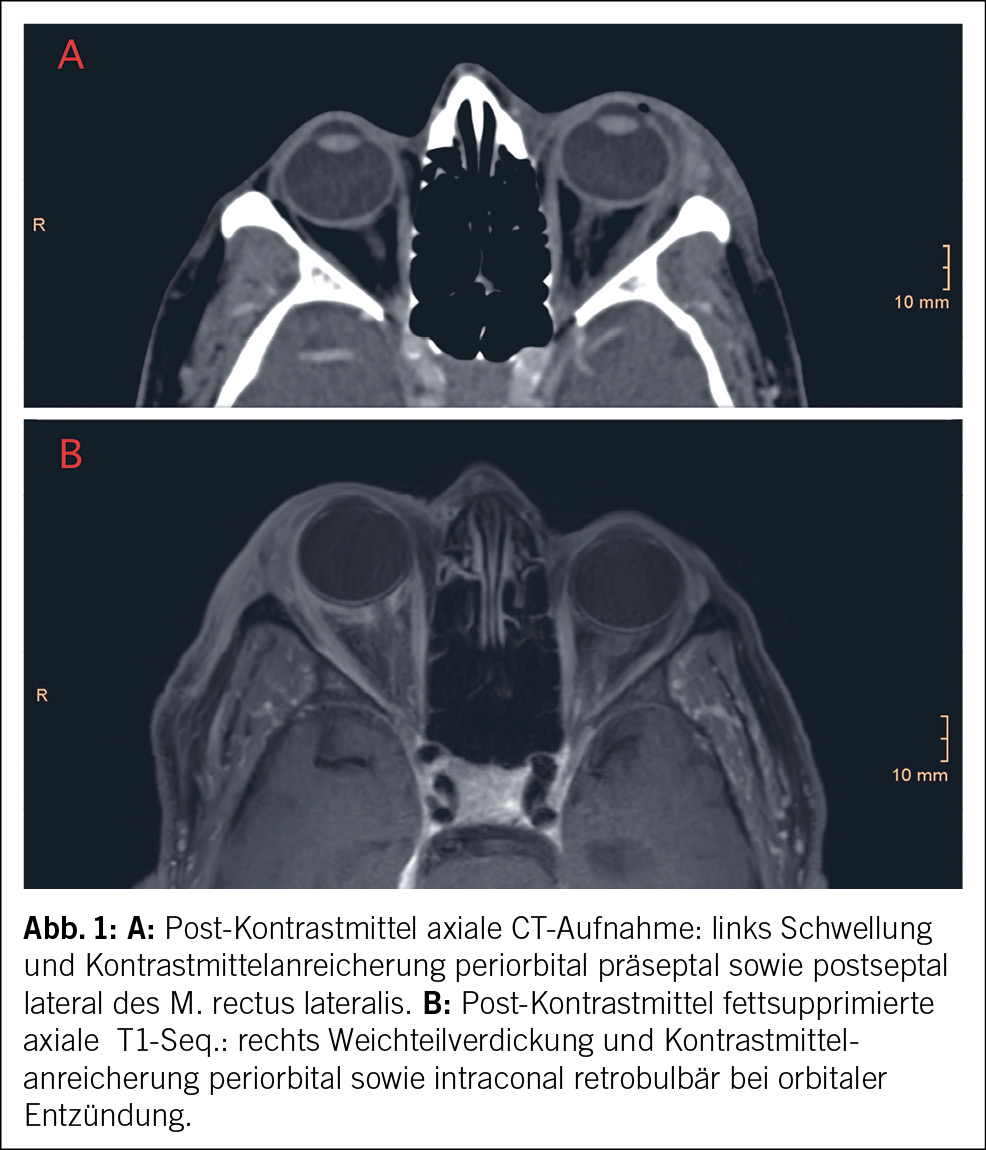

Im Hämatogramm fielen eine milde hyporegenerative normochrome und normozytäre Anämie (Hämoglobinwerte zwischen 110 g/l und 129 g/l), eine milde Thrombozytopenie (Thrombozyten 100–121 g/l) sowie eine Leukozytose (Leukozyten 15–17.3 g/l) auf. Der Gerinnungsstatus war unauffällig. Das mikroskopische Blutbild zeigte reichliche Vakuolen in den myeloiden Vorstufen. Ferner wurden schwankende CRP-Werte bis 74 g/l bei normwertigem Procalcitonin festgestellt. Die Substrate (Eisen, Vitamin B12, Folsäure) waren normwertig. Urinstatus und Urinsediment waren bland, ohne Hinweise auf eine Nephritis. In den weiteren serologischen Abklärungen waren die Komplementfaktoren sowie antinukleäre Antikörper und Anti-Neutrophile zytoplasmatische Antikörper negativ. Die ergänzende Eiweisselektrophorese im Serum und im Urin ergab einen normalen Befund. Die HIV-, Hepatitis-B- und Hepatitis-C-Serologien sowie der Quantiferon-Test zeigten sich negativ. In sämtlichen abgenommenen Blut- und Urinkulturen kam es zu keinem bakteriellen Wachstum. In den Bildgebungen zeigten sich keine Hinweise auf eine thorakoabdominale Raumforderung. Stattdessen wurde wiederholt eine orbitale Entzündung abwechselnder Lokalisation festgestellt (Abb. 1 A und B).

Konzept, Schreiben, Überprüfen, Editieren, dipl. Ärztin Elisa Leggeri; Radiologiebilder und Befunde, Überprüfen, KD Dr. med. Athina Pangalu; Supervision, Editieren, Überprüfen Prof. Dr. med. Florence Vallelian. Alle Autorinnen haben das eingereichte Manuskript gelesen und sind für alle Aspekte des Werkes mitverantwortlich.